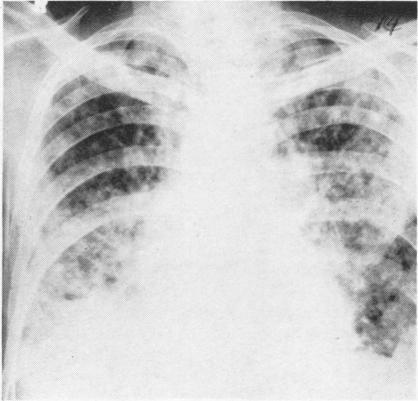

Thoracic actinomycosis.

Thorax. 1957 Jun;12(2):99-124. doi: 10.1136/thx.12.2.99.